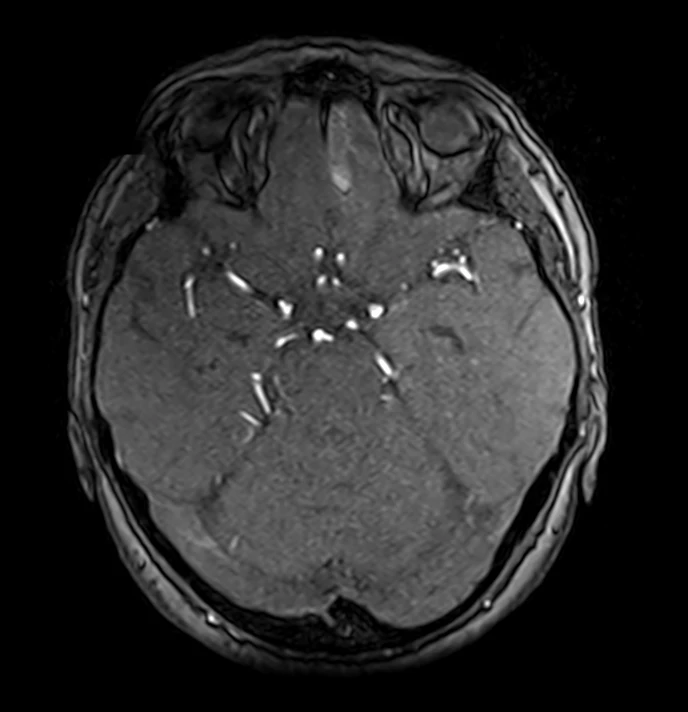

Клинический случай кавернозной мальформации, ассоциированной с венозной аномалией развития (ВАР). Следует напомнить, что ВАР часто сочетаются с каверномами, однако точные статистические данные не привожу, чтобы простимулировать самостоятельный поиск информации и закрепление знаний. Клиническая симптоматика у данного пациента отсутствует, что является типичным сценарием для подобных находок. Диагноз установлен случайно.